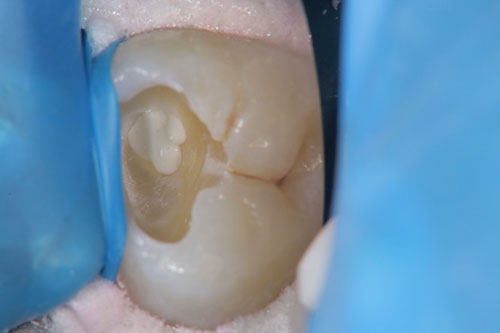

歯内療法は「歯を残すための治療」です。そのため、根管に影響が及び始めた時点で、神経を取り除く前に根管への感染を防ぐ「歯髄温存」も歯内療法の一部です。具体的にはMTAという特殊なセメントで、感染した歯髄のみを取り除き、抜髄を免れるための治療です。MTAセメント詳細